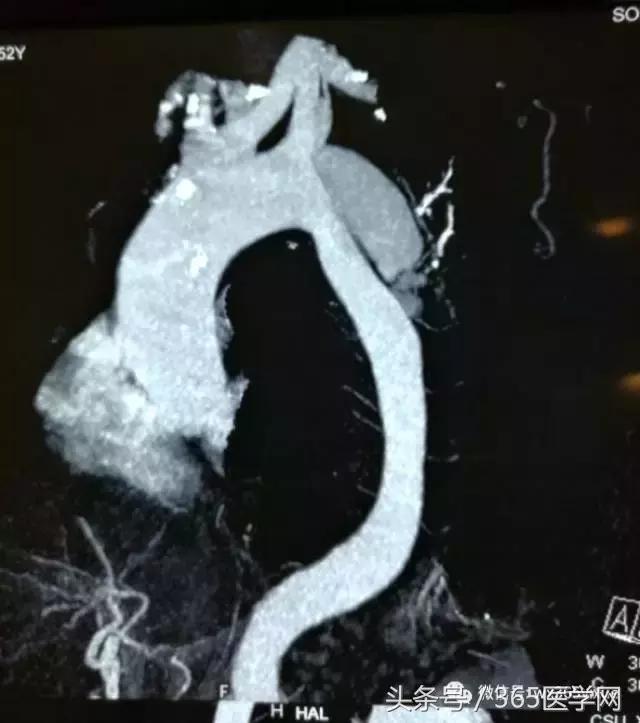

在临床上我们经常碰到主动脉Ⅲ型弓(图1C),即弓部成角陡峭,容易使主动脉支架外鞘在跨弓时打折,从而使支架释放时阻力增大,严重的甚至导致释放支架时移位,造成想象不到的严重后果。这样的情况就对支架材料提出了很高的要求。我们在临床实践中发现,上海微创公司的Hercules Low Profile 直管型覆膜支架系统(图5A)比较适合主动脉弓部成角陡峭的病人。原因有三:其一,它有着目前国内最小的输送系统外径,最小能够达到18F(直径20-36mm支架);其二,它有着覆膜套管跨弓设计,整个输送系统跨弓时阻力小,柔软不易打折,并且在支架释放瞬间稳定不易移位;其三,主动脉夹层是由于动脉壁出现破口,血流冲入导致形成真腔和假腔,由于假腔的压迫真腔一般会相对缩小,形成上粗下细的锥度。传统的胸主动脉支架系统如有些品牌支架没有锥度,头到尾直径没有变化,容易在释放时对相对缩小的真腔管壁造成应力拉扯,留下再发破口的隐患,因此经常需要在后段加入限制性裸支架人为形成锥度,不仅效果得不到很好保证,而且增加了患者经济负担。Hercules Low Profile独有大锥度支架规格,支架锥度范围2-10mm,锥度变化平缓,在释放 后能够更贴壁并且不造成过多拉扯,更适合主动脉夹层患者。对于下面的病例(图5B、C),患者主动脉角度陡峭,破口位置高,就需要选择本身比较柔软、容易过弓的支架,使用微创的公司Hercules Low Profile就能达到很好的效果。

图5B 主动脉弓角度陡峭

图5C 主动脉夹层破口位置高